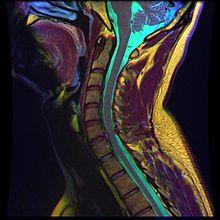

• Magnetic resonance imaging (MRI) without contrast is a diagnostic test that produces three-dimensional images of body structures using powerful magnets and computer technology. It can show the spinal cord, nerve roots, and surrounding areas, as well as enlargement, degeneration, and tumors. It shows soft tissues better than CAT scans. An MRI performed with a high magnetic field strength usually provides the most conclusive evidence for diagnosis of a disc herniation. T2-weighted images allow for clear visualization of protruded disc material in the spinal canal.